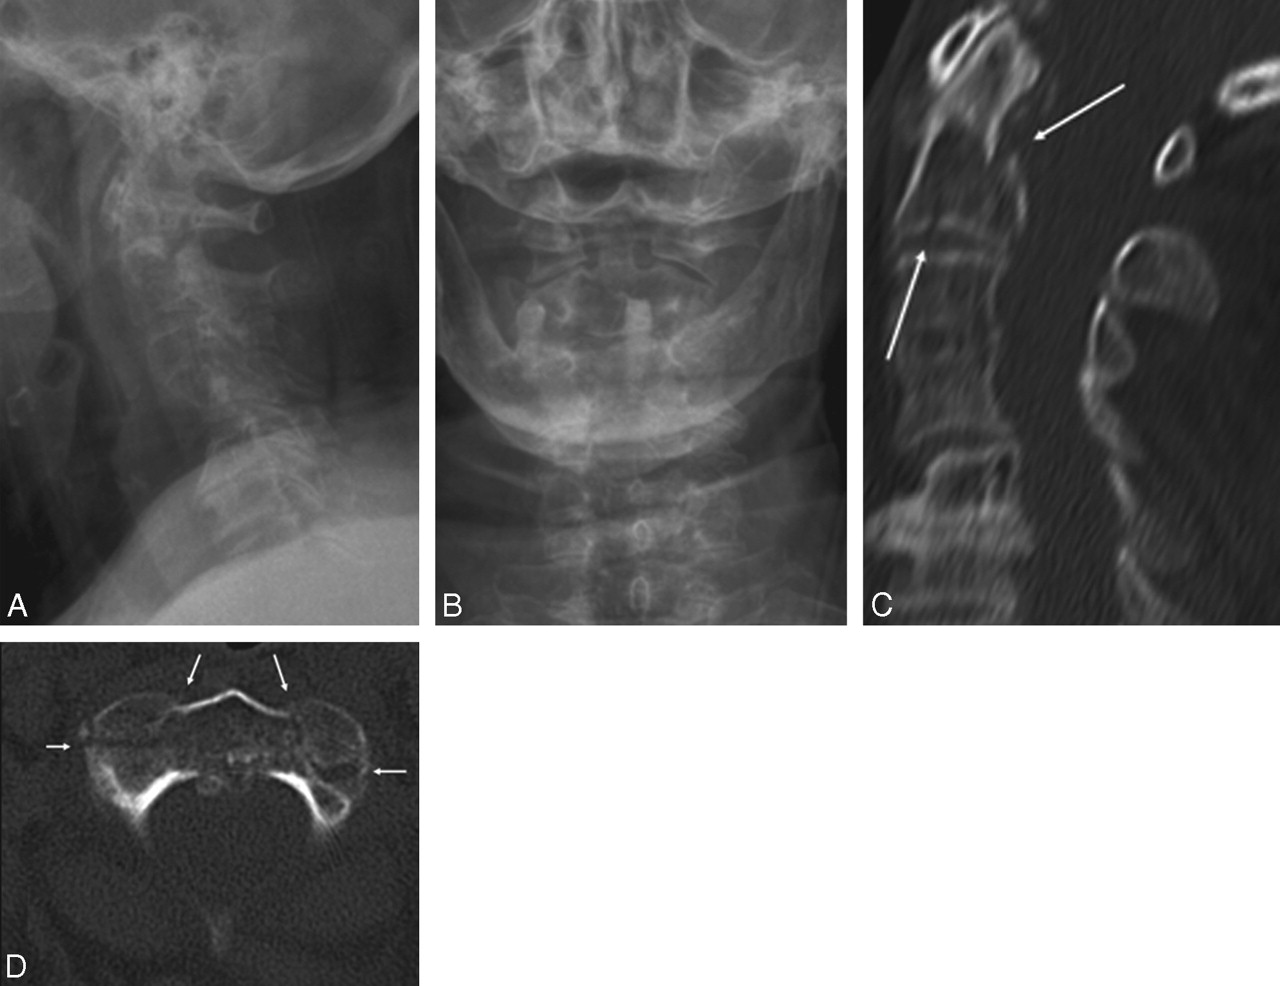

Of 191 patients, MDCT showed 18 patients with fracture(s) (9.4%), 3 in the standard-dose examinations and 15 in the low-dose examinations, with 4 fractures in the high-kilovolt group and 11 in the low-kilovolt group. Of these 18 fractures, 14 were unstable fractures (77.7%). Most fractures were situated at the C1–C2 level (n = 12): a large number of fractures at the base of the dens axis alone (n = 4; Fig 1) or in combination with other fractures (n = 2) at the level of C1 or C2 (Fig 2); 3 bilateral fractures of the arcus of C1 and/or C2; 2 pathologic fractures at the level of C2 (Fig 3); and 1 Hangman fracture. Two patients had an unstable burst fracture of a vertebral body (Fig 4). In 3 fractures, there was associated subluxation. Stable fractures were fractures of a spinous (n = 2; Fig 5 or of a lateral process (n = 2). The 2 experienced radiologists (R1 and R2) correctly identified all of the fractures in the first image interpretation at the moment of the presentation of the patient. The resident with 1 year of experience in CT (R3) also correctly identified all of the fractures. The first-year resident with no CT experience (R4) missed 3 fractures: 1 unstable fracture at the base of the dens axis (C2) and 2 stable fractures, 1 of a spinous and 1 of a transverse process. In 4 patients, standard radiography of the cervical spine at the moment of the presentation of the patient was interpreted as negative, whereby MDCT clearly depicted a fracture, 2 of them unstable fractures at the base of the dens axis (Fig 6).

A, An 82-year-old woman with acute neck pain after a motor vehicle crash. Standard radiography, lateral view, was interpreted as negative, but additional CT was proposed because of technical failure to view the lower cervical segment C7 (superposition of the shoulders). B, Standard radiograph with odontoid view was interpreted as negative for fracture in the region of the cranio-cervical junction. C, Sagittal 2.5-mm image of low-dose 16-MDCT-examination (100 kV and 165 mAs) clearly depicts fracture (arrows) at the base of the axis (C2). D, Axial 2.5-mm image of the same low-dose CT examination shows more complex fracture of the body of C2, bilaterally extending in the lateral masses (arrows). Calculated effective dose of MDCT examination is 1.3 mSv.